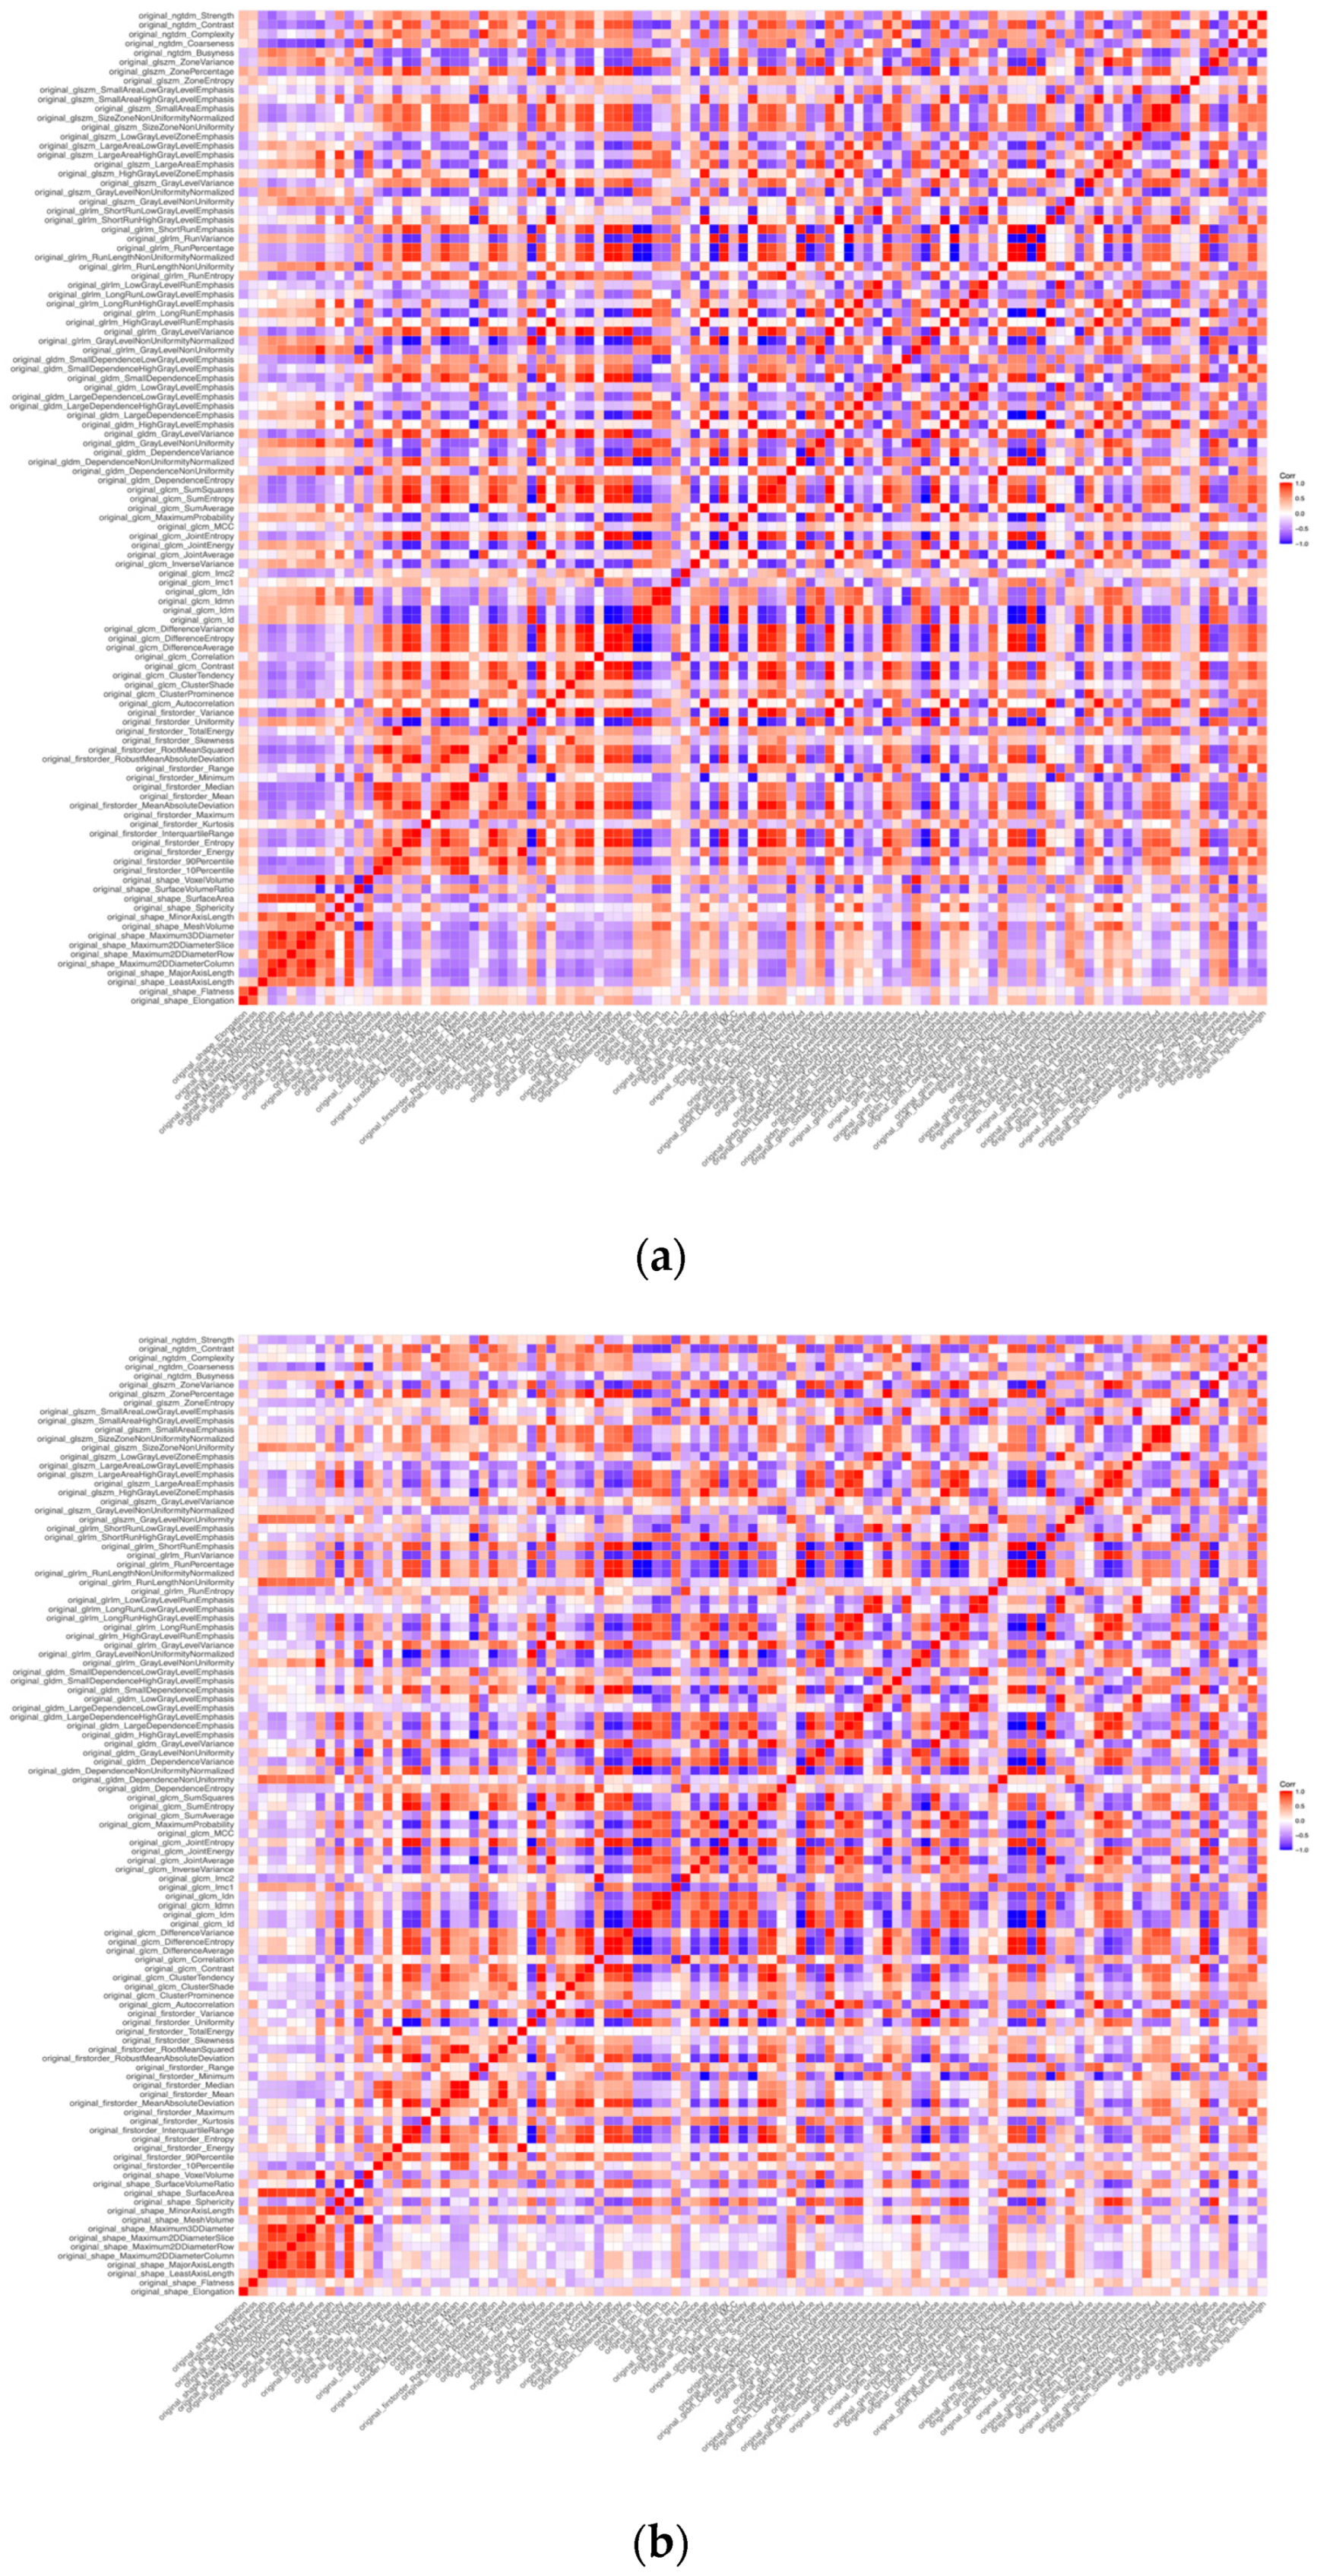

3.2. Cluster Analysis